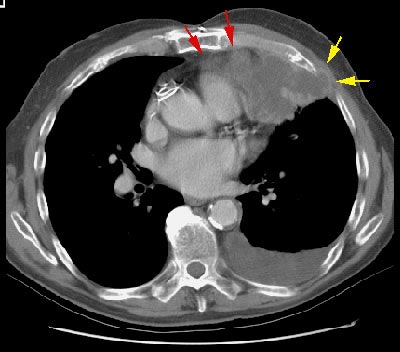

Example 2: In this patient with non-small cell lung cancer there is extension of the tumor between the ribs into the chest wall (yellow arrows). Disruption of the fat planes within the mediastinum (red arrows) is highly suggestive of mediastinal invasion as well. The lesion also abuts the main pulmonary artery.